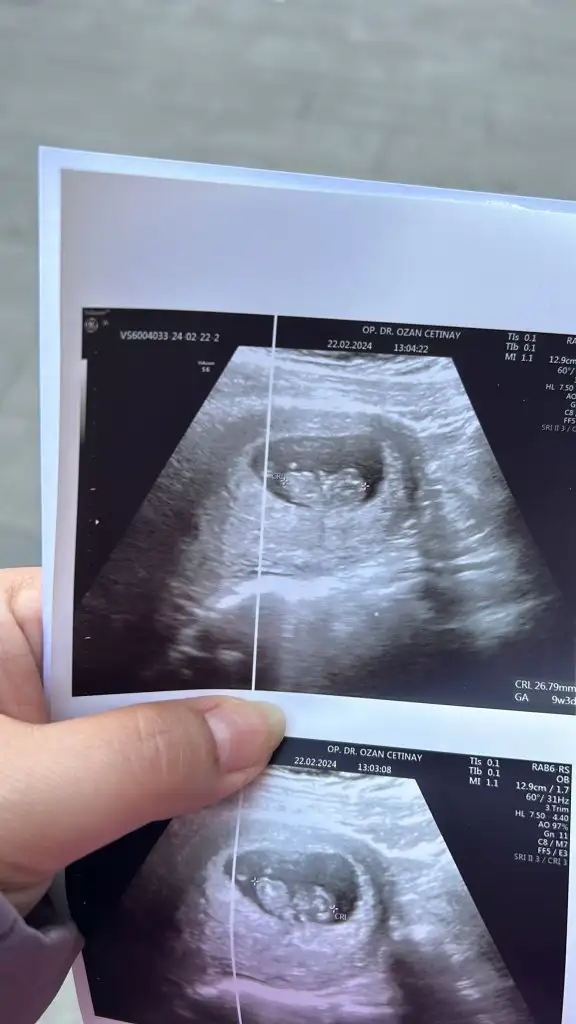

İyi gidiyor çok şükür 12+3 devam ediyoruz.Canım selam nasıl gidiyor gebelik kaç haftalık oldun

Valla onları demedi neden demedi bilmiyorum kendi baktı herşey yolunda dedi cinsiyetide söylemiyordu ben sordum kıza benziyor ama bu haftalarda yanılma olur değişebilir bidaki gelmene netleşir dedi bakalımYaaa ben onu yerim ne kadar net maşallah canım kaç cm ve kaç gram dedi doktor

Evet ya heveslenmiştim ama doktor kız deyincede üzülmedim 2. Kızım olcakNasip canım kese teorisi bile tutmuyor